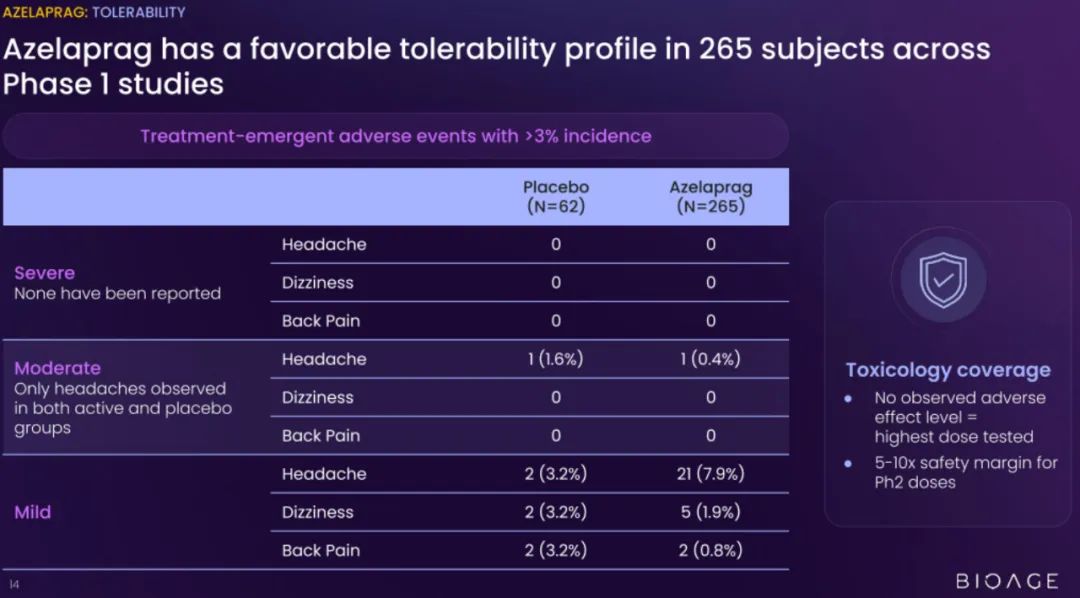

BioAge Labs的主要关注点是代谢疾病,这是全球最大的医疗保健挑战之一。BioAge Labs的主要候选产品 Azelaprag是一种口服小分子,在8个 1 期临床试验中,265 名受试者的耐受性良好。在临床前肥胖模型中,azelaprag 显示出能够使胰高血糖素样肽-1 受体 (GLP-1R) 激动剂诱导的体重减轻增加一倍以上,同时恢复健康的身体成分并改善肌肉功能。